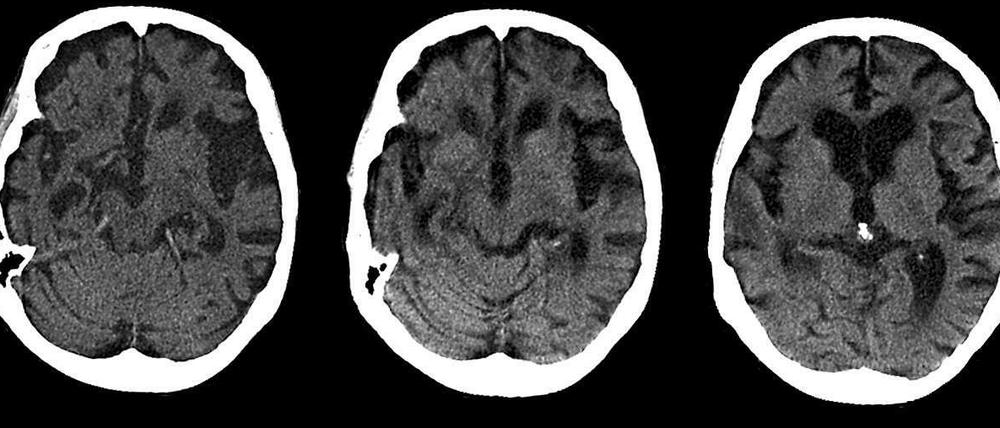

Alzheimer: Ultraschall als Hoffnungsschimmer

Im Tierversuch ist es gelungen, Alzheimer-typische Ablagerungen zu entfernen. Ob das auch beim Menschen klappen wird, ist jedoch unklar.

Ultraschall könnte zukünftig eine Methode sein, um die Alzheimer-Krankheit zu behandeln. Diesen Schluss legt eine Studie an Mäusen nahe, die eine Alzheimer-ähnliche Erkrankung hatten. Wissenschaftler der Universität Queensland in Brisbane, Australien, behandelten die Gehirne der Tiere mit Ultraschall. Daraufhin verschwanden Amyloid-Plaques, giftige Alzheimer-typische Eiweißablagerungen, aus dem Gehirn. Auch das Gedächtnis der Tiere verbesserte sich, berichten die Forscher im Fachblatt „Science Translational Medicine“.